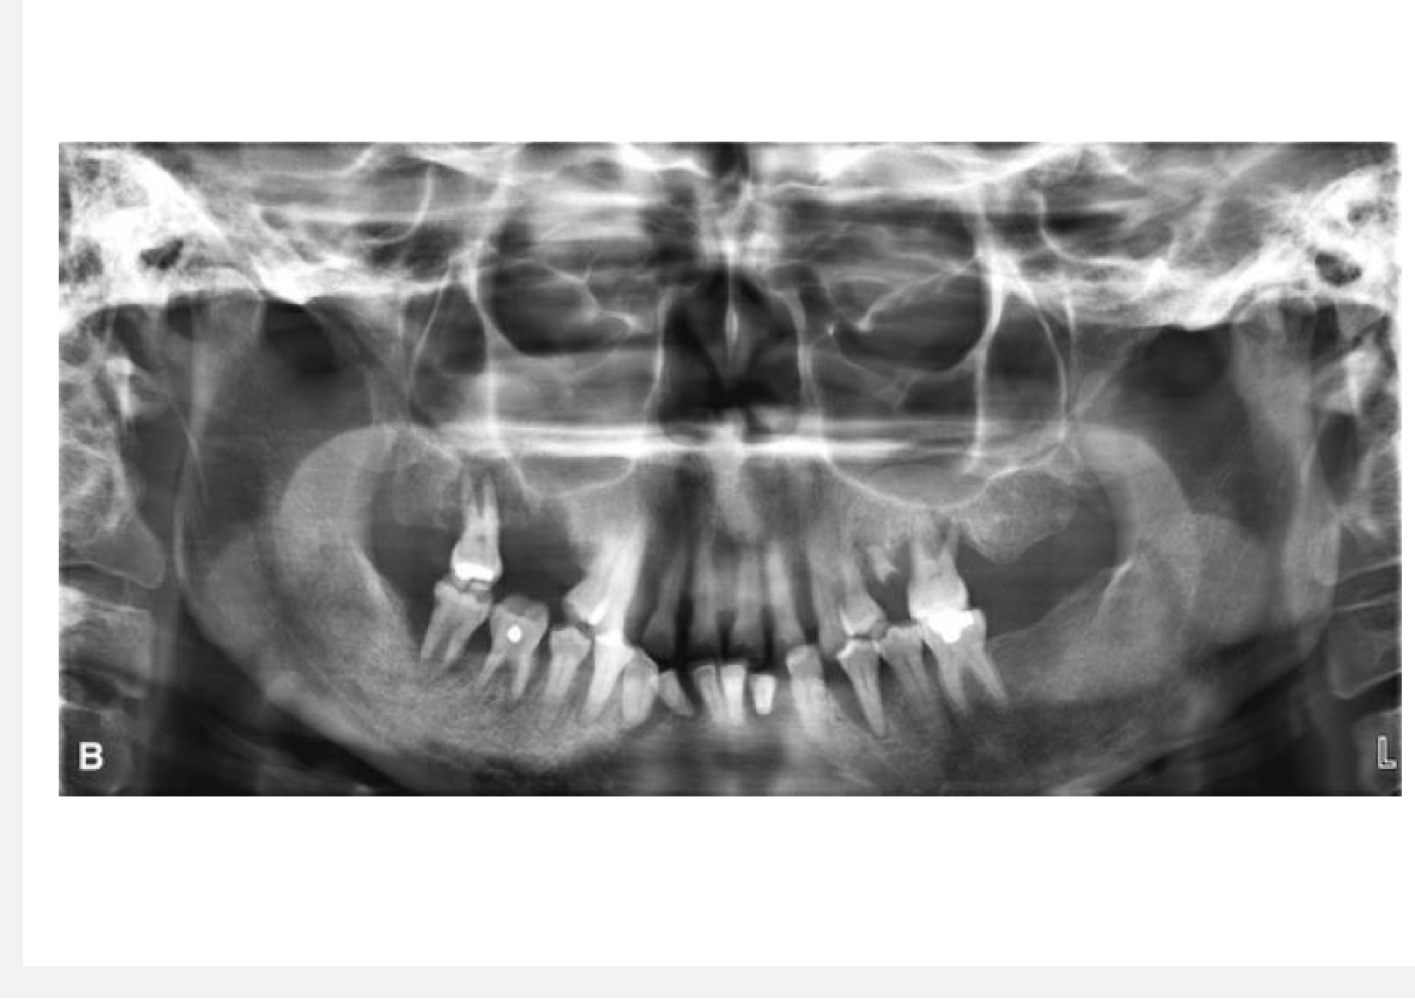

Why would we use a panoramic image?

To see dentition, joints, cysts, trauma, can't get intraoral images

What are the advantages of panoramic images?

Broad coverage, low radiation dose, easy, quick

What are disadvantages of panoramic images?

Magnification of image, low resolution, ghost images, positioning errors, difficult to decipher

What happens when the mandible is at the center of the focal trough?

Minimal distortion of image

What happens if the mandible is posterior to focal trough?

Widening of image

What happens if the mandible is anterior (too front) to the focal trough?

Lengthening of image

Why do we use an upward projection of the beam in panoramic images?

So that the beam spreads out and we can see vertical relationships of mandible and maxilla

If pt is rotated upward for a pan, what happens?

Overlapping images and hard palate obscures roots of teeth

If the pt is rotated downward for a pan, what happens?

The anterior teeth are distorted and cutting off symphyseal region

What happens if the tongue is not placed on the roof of the mouth?

Air is present and you cant see roots of teeth